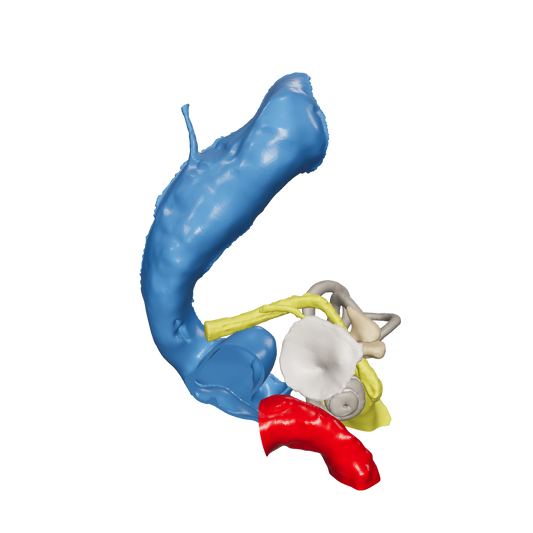

Dissect each one to learn human temporal bone anatomy, hearing and vestibular systems.

*High Contrast Colors* 3D Temporal Bones to Introduce Anatomy (6-pack)

Regular price $402.00 USDRegular priceUnit price per -